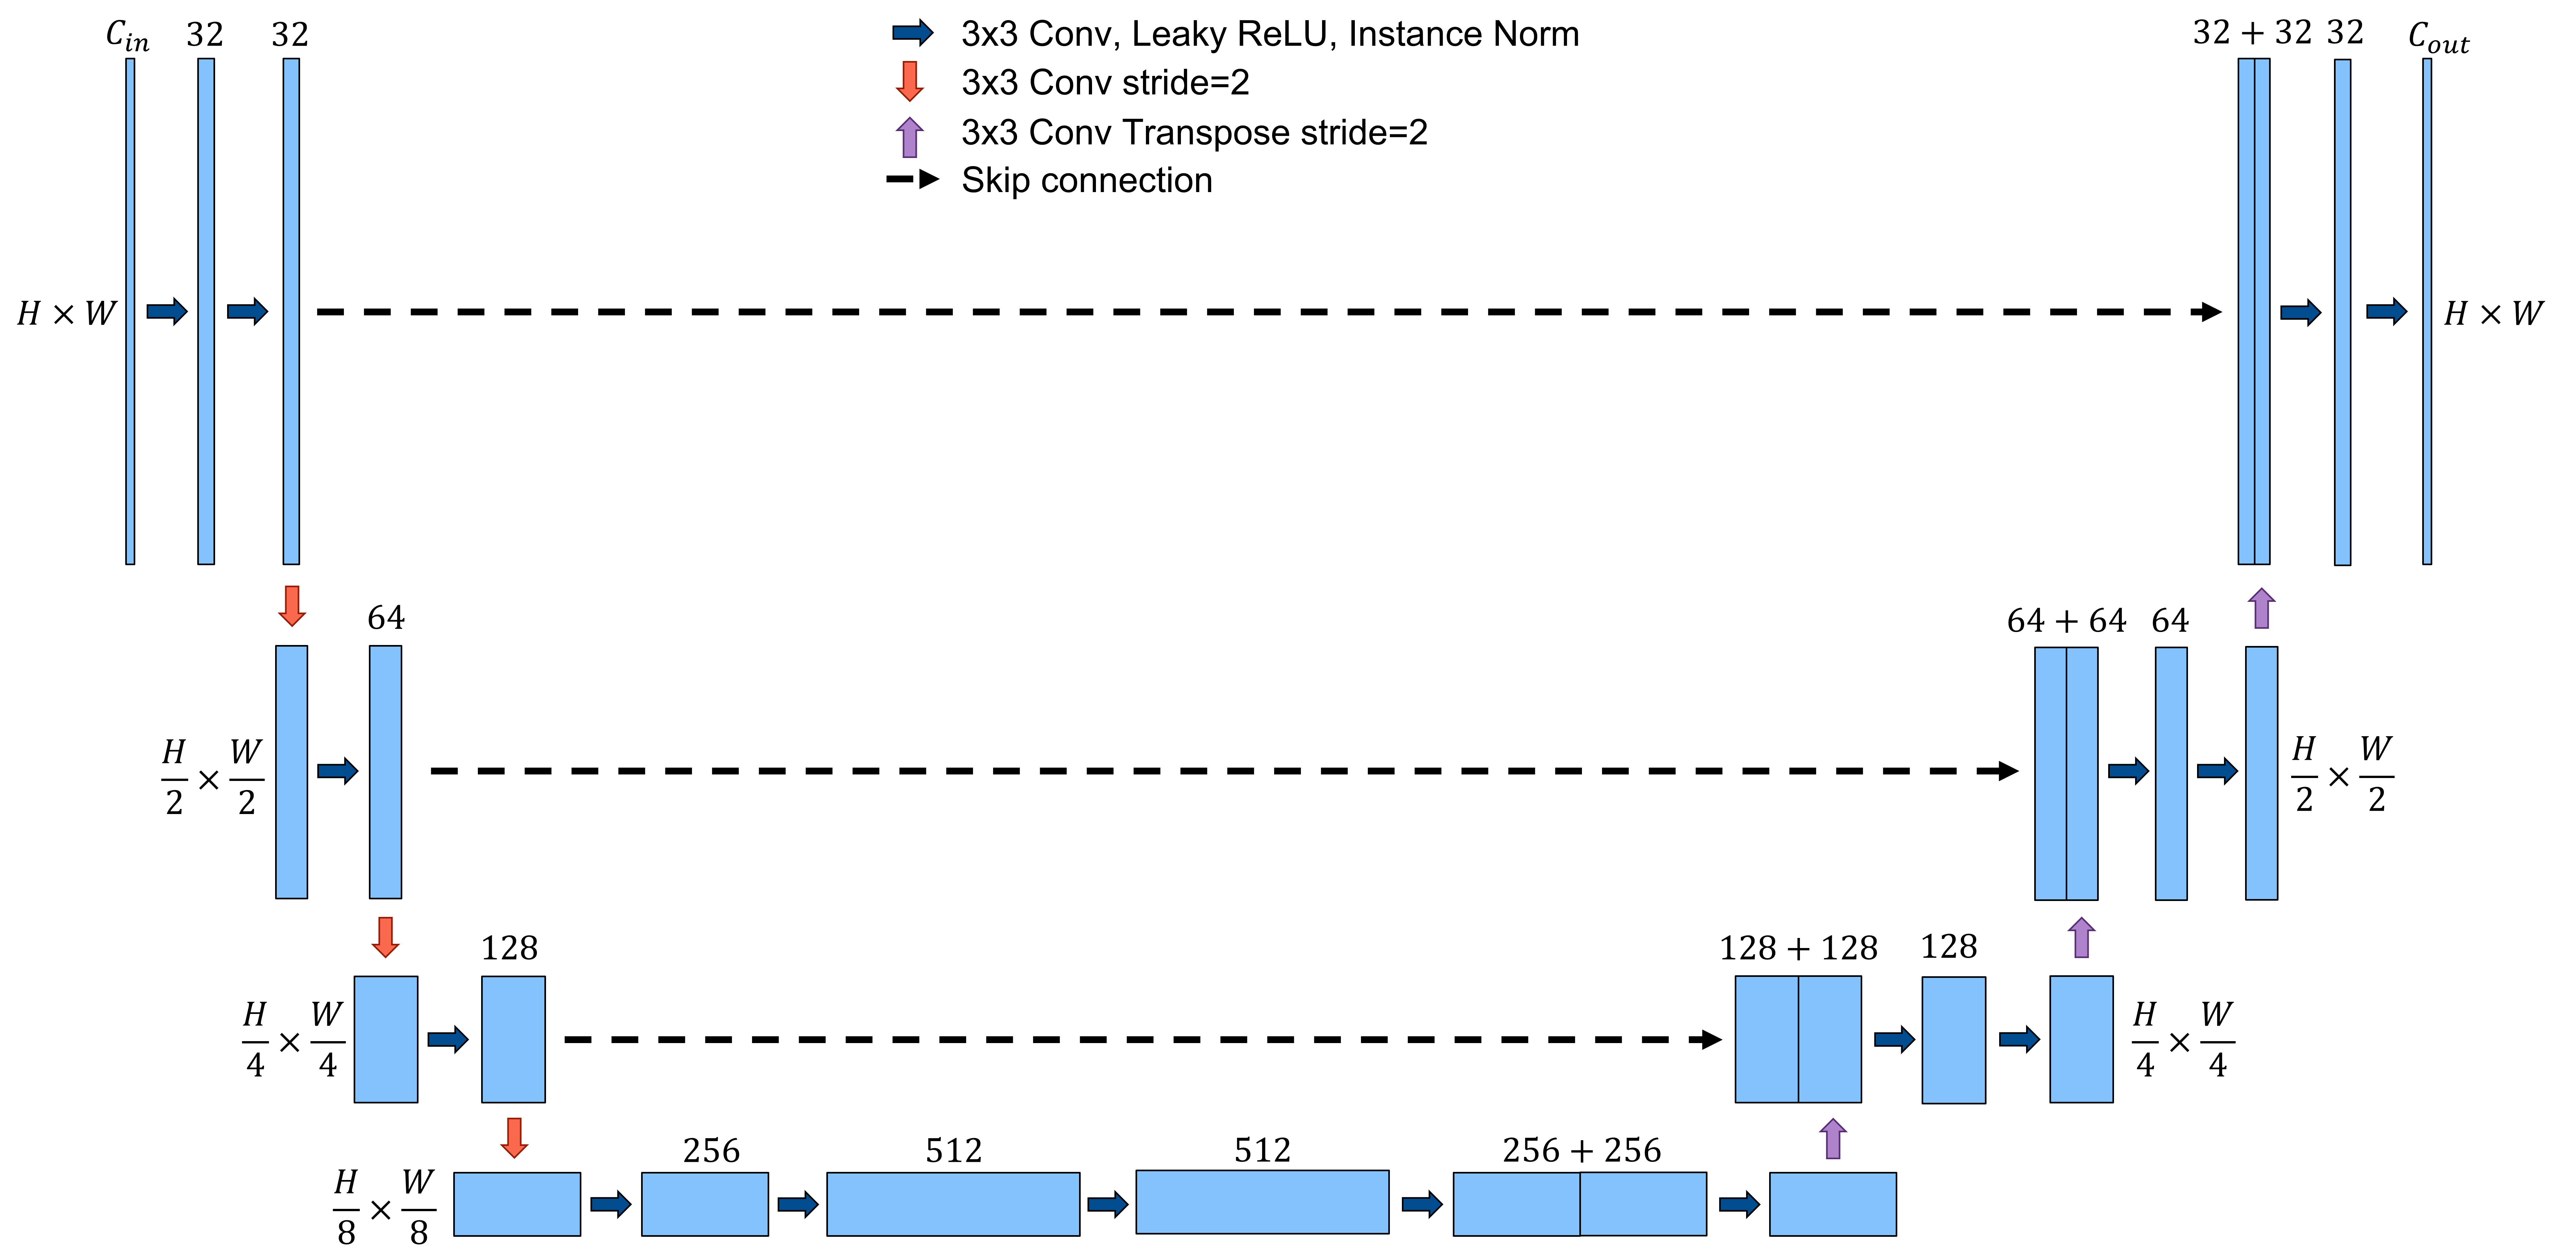

Instead of limiting bias fields to the outer rings of the FOV, we randomly apply them at every possible position as part of data augmentation. Furthermore, we employ random rotation, flipping, elastic transformation, scaling, and motion artifacts during the training of the segmentation network. We use a variation of the very successful U-Net architecture [18] and follow the guidelines of nnU-Net to configure our network optimally for the given task [19].

2.2 Task A: Lesion Segmentation

We define the segmentation task as a multi-label classification problem, where each pixel can be part of the classes IRMA, NA, NV, or neither. We choose the widely successful U-Net architecture, which is known for its reliable segmentation performance on medical image datasets [20, 19]. For the optimal training parameters, we follow the guidelines of nnU-Net that define preprocessing steps, network architecture, loss function, and learning rate. Our final architecture can be seen in Figure 3, where for our baseline model, for the network using the additional segmentation map input, and . Our loss function is the sum of the soft Dice loss and the channel-wise binary cross entropy loss.